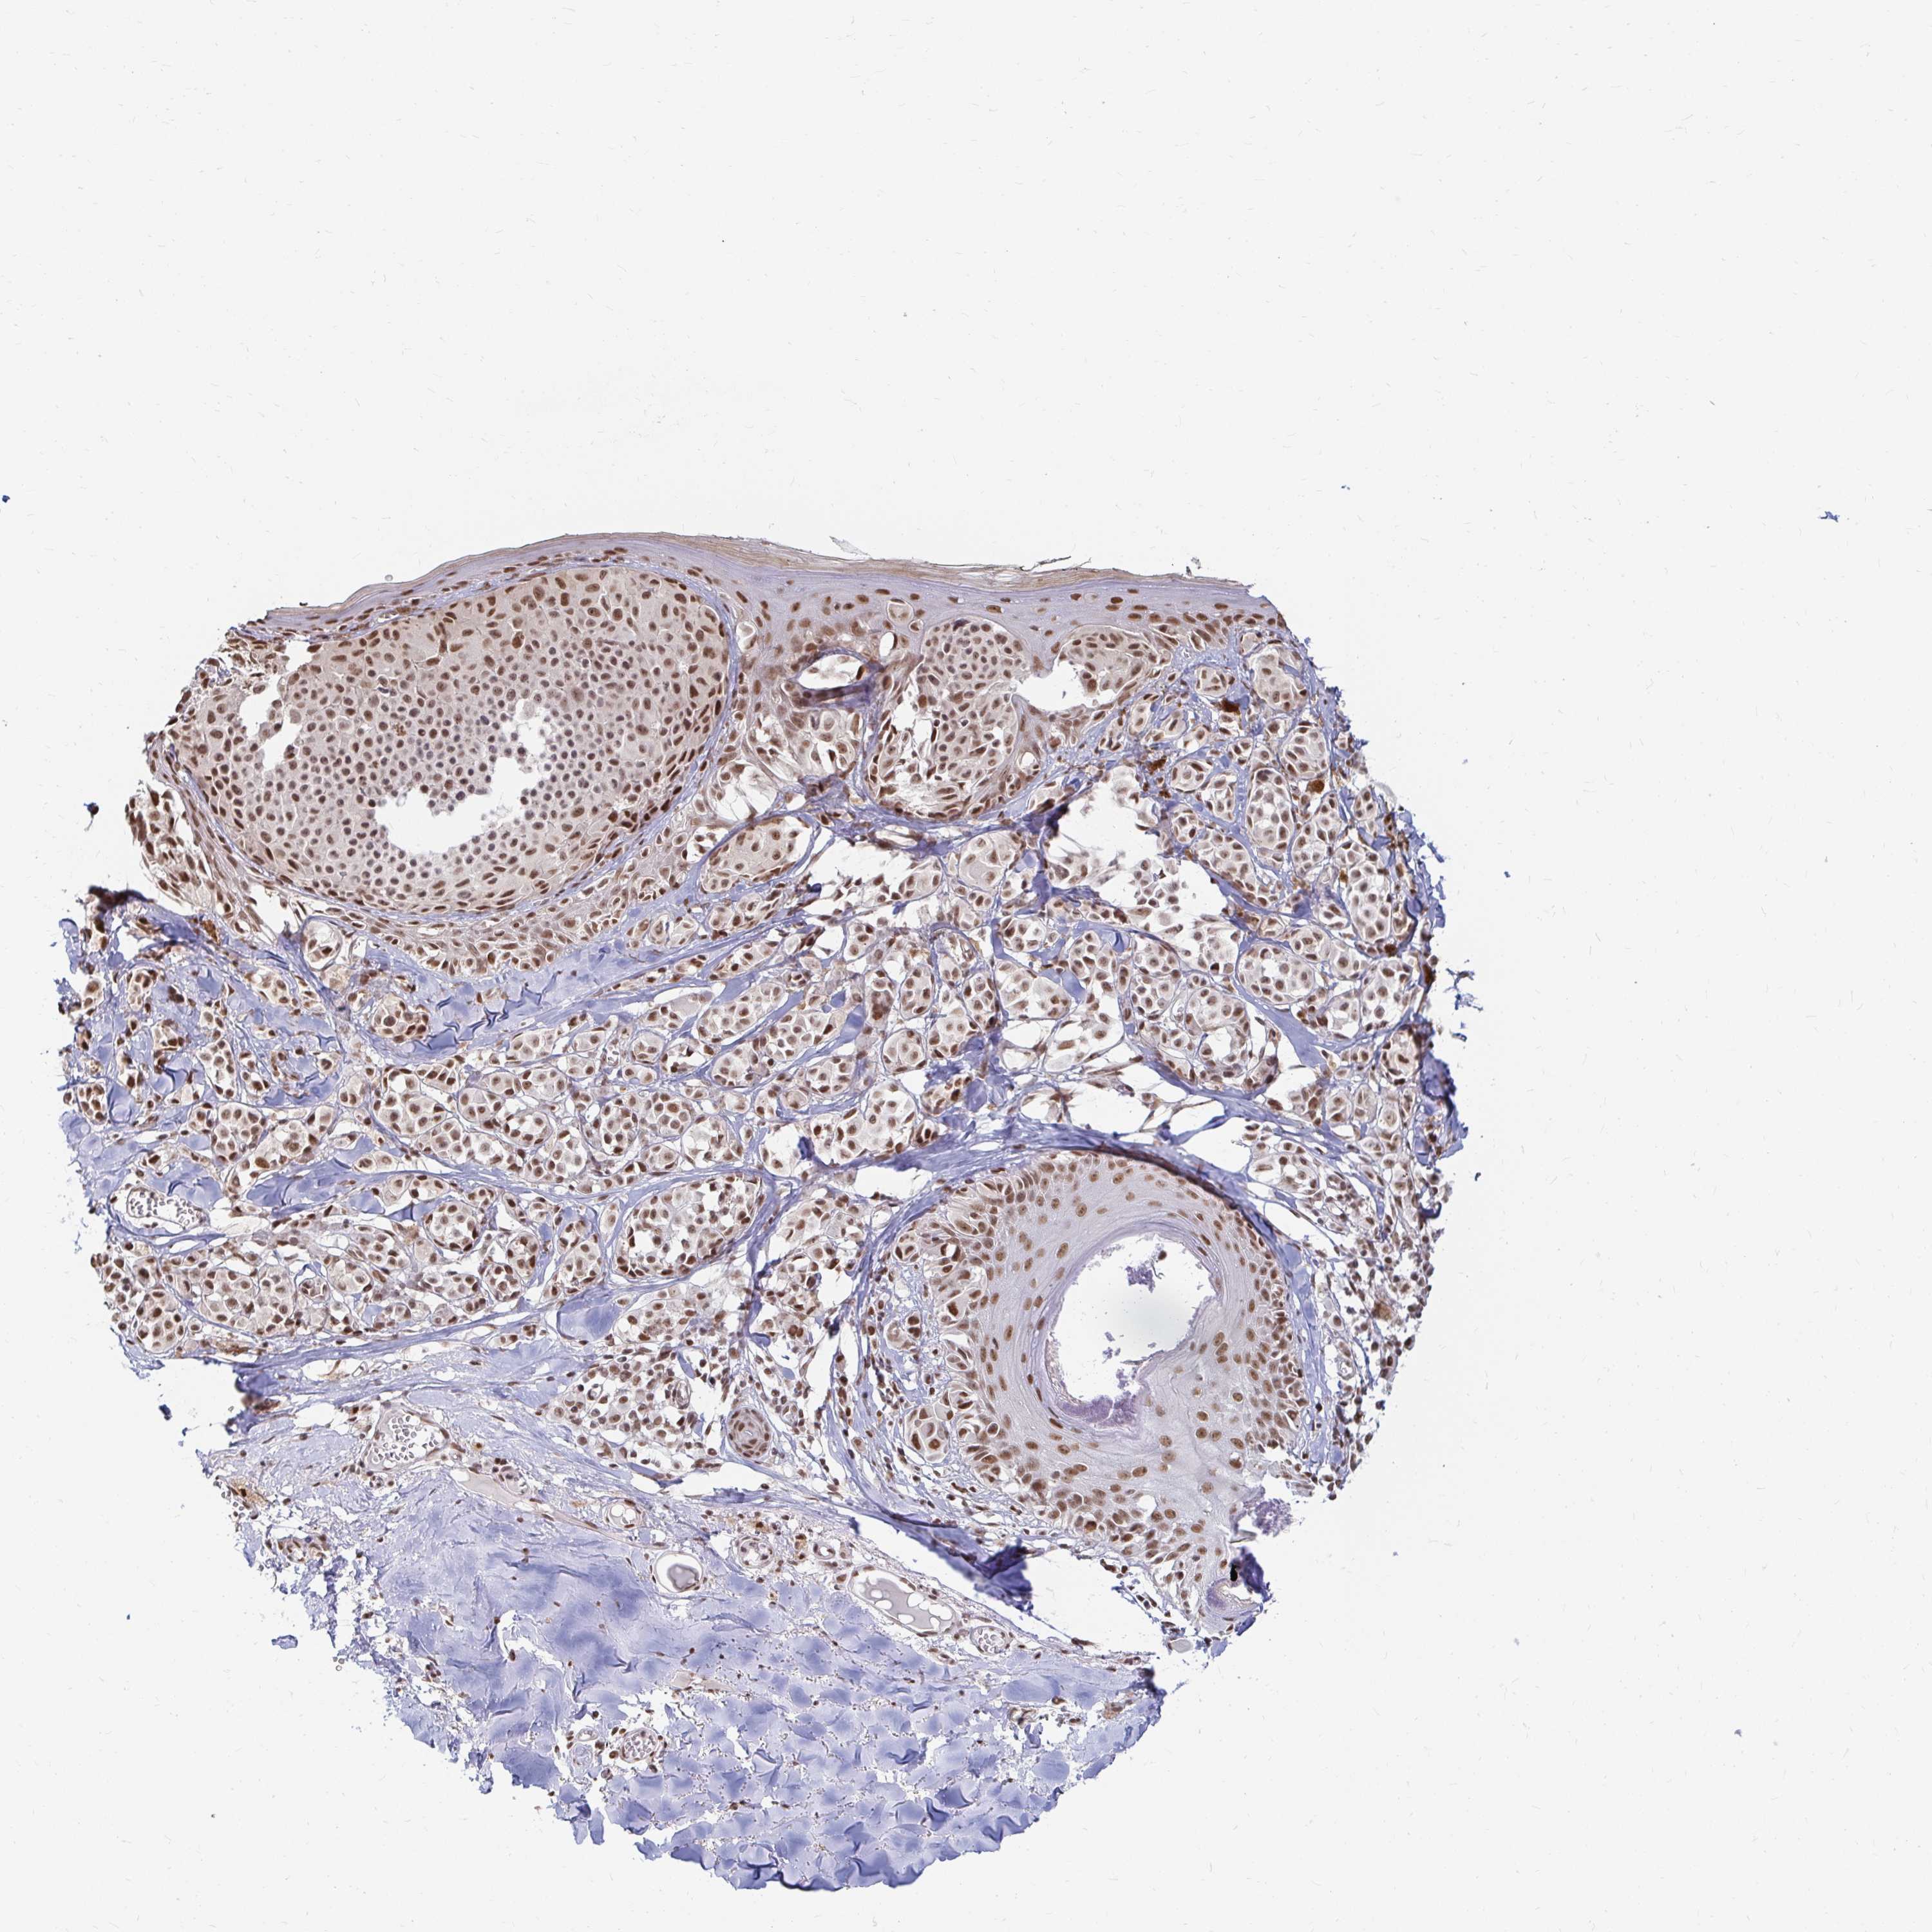

MELANOMA - Protein expressioni

A mouse-over function shows sample information and annotation data. Click on an image to view it in a full screen mode. Samples can be filtered based on level of antibody staining by selecting one or several of the following categories: high, medium, low and not detected. The assay and annotation is described here.

Note that samples used for immunohistochemistry by the Human Protein Atlas do not correspond to samples in the TCGA dataset.

Antibody stainingi

Antibody staining in the annotated cell types in the current human tissue is reported as not detected, low, medium, or high, based on conventional immunohistochemistry profiling in selected tissues. This score is based on the combination of the staining intensity and fraction of stained cells.

Each image is clickable and will lead to virtual microscopy that enables deeper exploration of all samples and also displays staining intensity scores, fraction scores and subcellular localization as well as patient and tissue information for each sample.

Antibody HPA041057

Antibody HPA058707

Antibody CAB011532

Staining

High

Medium

Low

Not detected

Intensity

Strong

Moderate

Weak

Negative

Quantity

>75%

75%-25%

<25%

None

Location

Nuclear

Cytoplasmic/membranous

Cytoplasmic/membranous,nuclear

Malignant melanoma, NOS

Malignant melanoma, Metastatic site